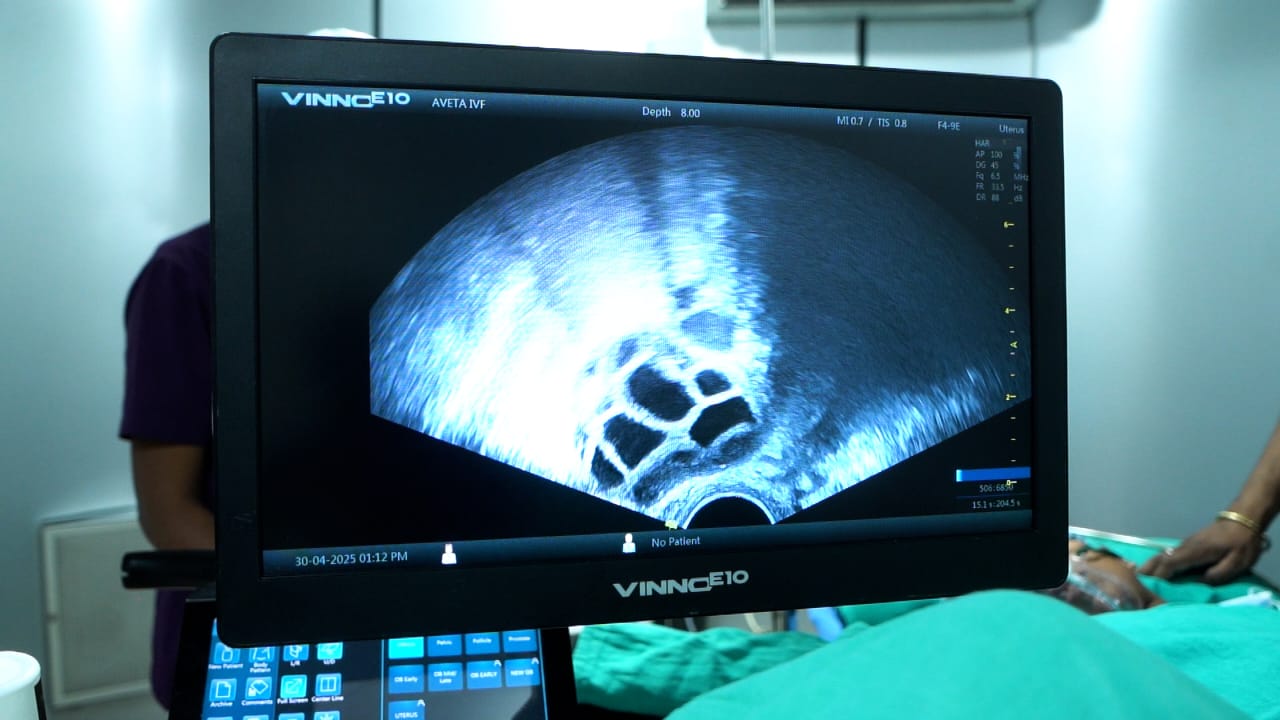

Modern technology, skilled medical staffs, individualised patient care, high success rates and a dedication to moral behaviour are all reasons why Aveta IVF in Ranchi is exceptional. It’s the best option in the area for treating infertility.

- Advanced Technology